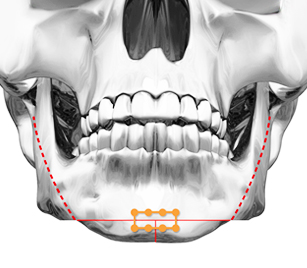

사각턱은 아래턱뼈의 크기가 크고 각이 져서 정면으로 보았을 때 사각형처럼 보여 각진 윤곽을 만드는 것을 말합니다.

포에버 사각턱성형은 단순히 뼈를 절제하는 것이 아닌 개개인의 얼굴뼈 발달 정도,

신경선 위치, 근육, 지방 두께 등을 모두 고려한 수술로 자연스럽고 매끄러운 얼굴 라인을 만듭니다.

CASE 01 긴곡선절골술

CASE 01 긴곡선절골술얼굴 아랫부분이 넓고

각져보이는 경우 -

CASE 02 피질골 절제술

CASE 02 피질골 절제술정면에서 볼때 얼굴이

넓어보이는 경우 시행 -

입안 최소절개로 절제 공간 확보 후,

신경선을 피해 턱뼈 절제 -

케이스에 따라

피질제거술/교근축소술 병행 -

이중턱, 이차각

가능성을 최소화한

매끈한 얼굴라인 완성